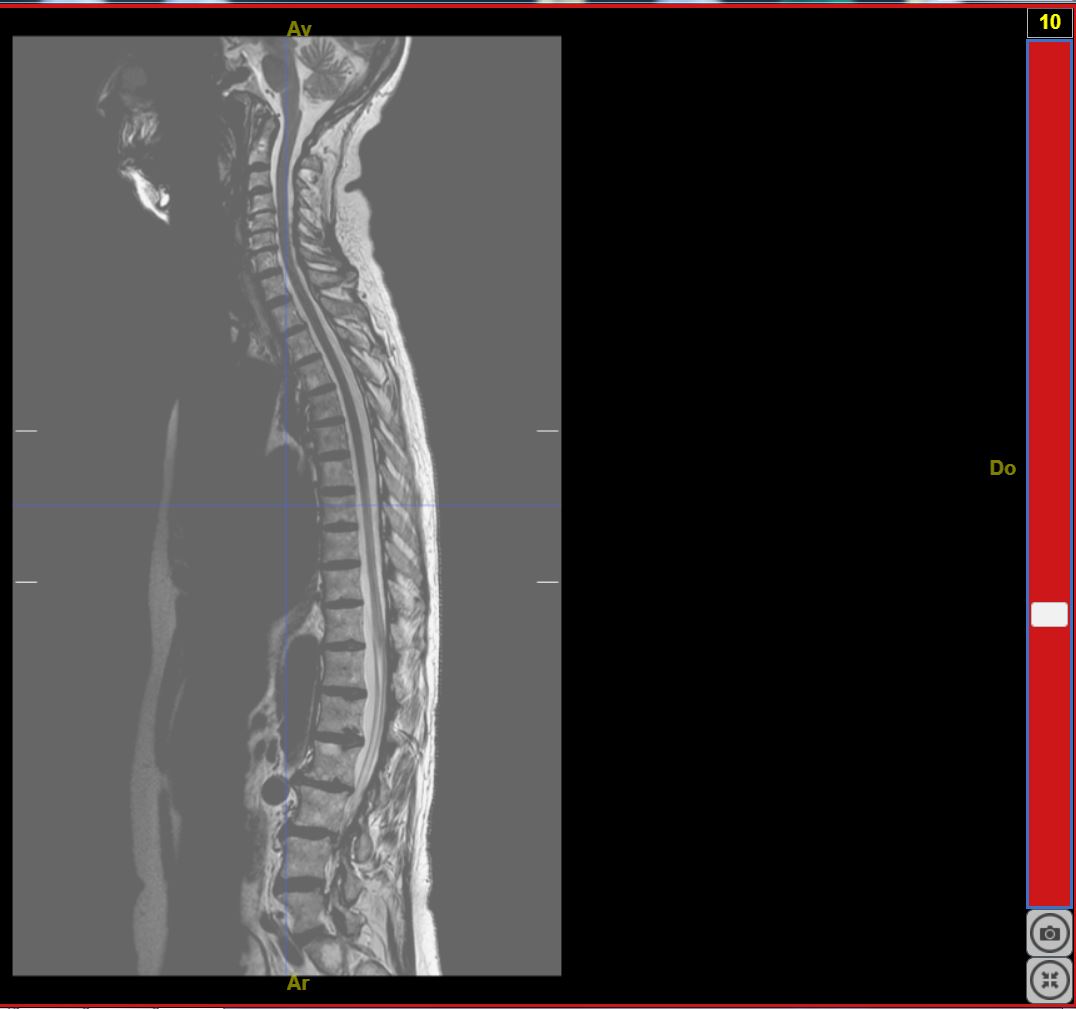

IRMsujet12132MoelleEpiniereSaineComplete T2